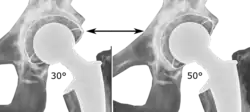

Post-operative projectional radiography is routinely performed to ensure proper configuration of hip prostheses.

The direction of the acetabular cup influences the range of motion of the leg, and also affects the risk of dislocation.[16] For this purpose, the acetabular inclination and the acetabular anteversion are measurements of cup angulation in the coronal plane and the sagittal plane, respectively.

![Acetabular inclination.[95] This parameter is calculated on an anteroposterior radiograph as the angle between a line through the lateral and medial margins of the acetabular cup and the transischial line which is tangential to the inferior margins of the ischium bones.[95]](./_assets_/Acetabular_inclination_of_hip_prosthesis.jpg)

![Acetabular inclination is normally between 30 and 50°.[95] A larger angle increases the risk of dislocation.[16]](./_assets_/Range_of_acetabular_inclination.png)